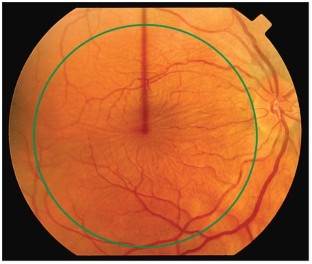

A variety of retinal signs can occur in patients who have systemic vasculitides, or who experience complications of these diseases or their treatment. Although treatment of these retinal manifestations is usually the treatment of the systemic disease, specific treatment is occasionally indicated to preserve vision. The more prevalent of the systemic vasculitides are giant cell arteritis, polyarteritis nodosa, Wegener's granulomatosis, Churg–Strauss syndrome, relapsing polychondritis and systemic lupus erythematosus. Less frequently occurring vasculitides include Takayasu's arteritis, Goodpasture's disease, microscopic polyangiitis and Henoch–Schönlein purpura, as well as vasculitis secondary to scleroderma and rheumatoid arthritis. This article describes the pathogenesis, clinical features and treatment of retinal manifestations of systemic vasculitides.

The types of posterior segment clinical signs relating to the various vasculitides are influenced by the diameter of vessel involved

The vasculitic process typically affects the retinal arteries rather than the veins, and these signs are not specific to any type of vasculitis